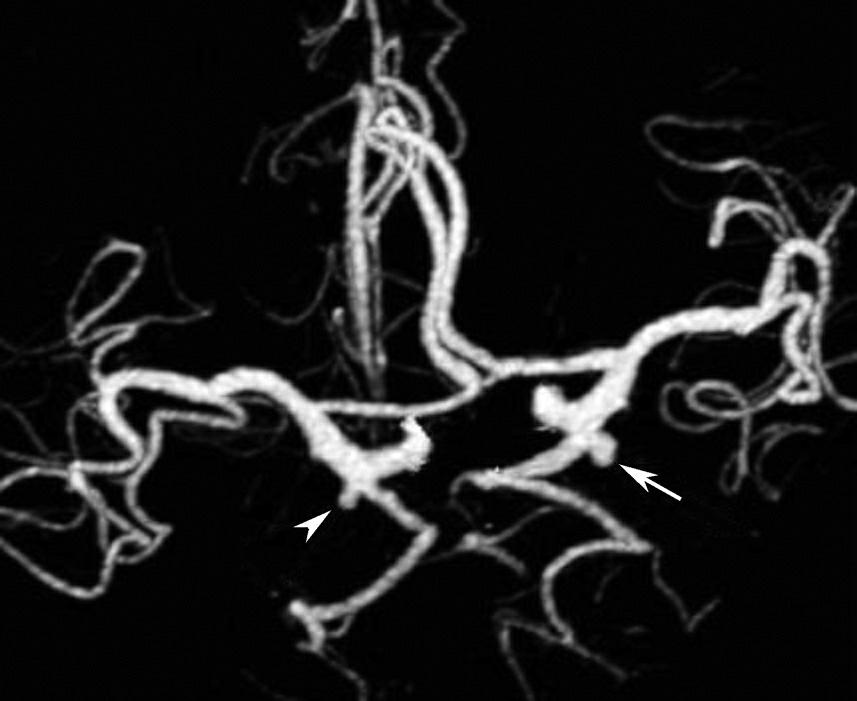

基底动脉开窗畸形的发生机制被认为是胚胎第5周时成对的胚胎性神经动脉融合障碍,或为原始侧动脉残留所致(图1-2-78)。

图1-2-78 基底动脉开窗畸形(箭)

永存三叉动脉是颈内动脉海绵窦段与基底动脉之间的胚胎性吻合,为颈内动脉系统与椎基底动脉系统之间最常见的异常交通,是根据它伴行的颅神经而命名的。其他异常吻合包括永存听动脉、永存舌下动脉及永存寰前节间动脉(图1-2-79)。

图1-2-79 永存三叉动脉

A、B.异常吻合支沟通至右侧海绵窦(箭);基底动脉(长箭)